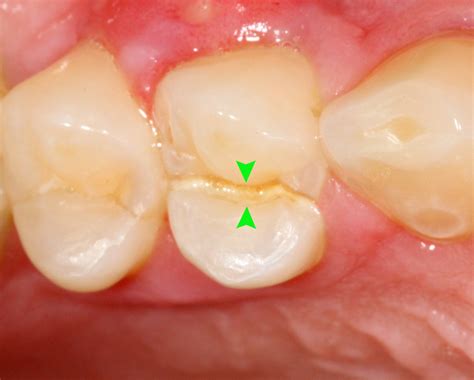

Craze Lines Superficial lines only in the enamel. No treatment needed (cosmetic).

Fractured Cusp A piece of the tooth’s chewing surface breaks off. Dental crown or filling.